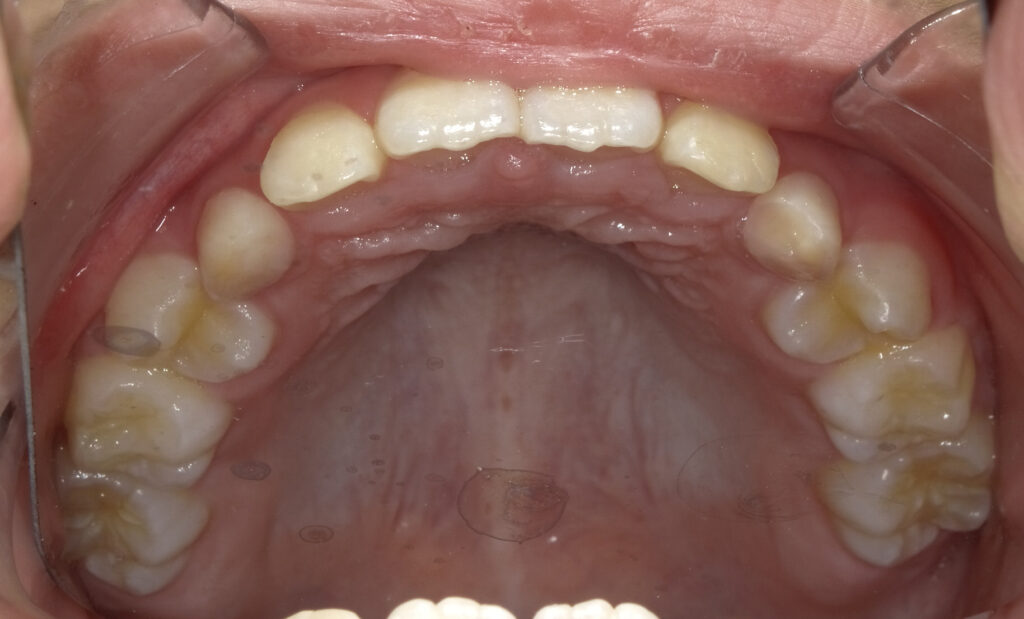

上顎

治療前